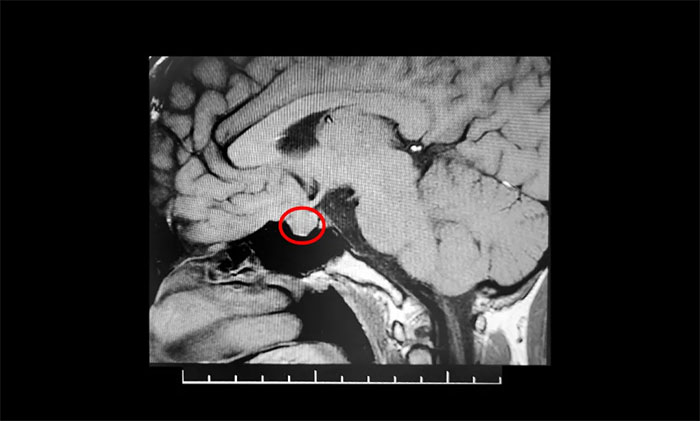

鞍區(qū)MRI平掃+增強(qiáng)顯示:垂體前葉內(nèi)見一矢橫高徑約1.2*1.9*1.1cm異常信號灶,邊緣光整,鞍底下陷。垂體柄縮短,視交受壓上抬。檢查催乳素超3000μIU/mL,遠(yuǎn)超正常值。

結(jié)合患者以往影像資料和內(nèi)分泌科檢查結(jié)果,由潘仁龍主任、李士其教授、吳治群博士組成的專家團(tuán)隊(duì)會診判斷,婷婷患了泌乳素垂體瘤。

▲ 垂體大腺瘤超蝶鞍生長